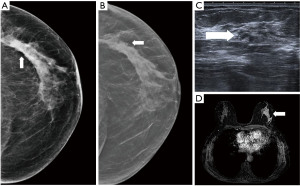

- Screening, an asymptomatic woman of 65 years old, in mammography an architectural distortion is detected in the lateral part of the left breast. The ultrasound findings are subtle with suggested areas of decreased echogenicity. The biopsy under ultrasound guidance reveals DCIS grade 2. The extent of the disease however is not certain. MRI is indicated. MRI shows an extensive process in the lateral part of the left breast resulting in the need of mastectomy (Figure 10).

Figure 10 Mammography of the left breast in cranio-caudal view (A) with architectural distortion (arrow). The distortion is more visible in DBT (B) (arrow). Ultrasound (C) reveals subtle finding of irregular area of decreased echogenicity (arrow). MRI (D) shows extensive area of non-mass-like enhancement in the whole lateral part of the breast (arrow). DBT, digital breast tomosynthesis; MRI, magnetic resonance imaging. - Diagnostic assessment, a patient of 45 years of age with a palpable lump on the right side for 2 months. In mammography with higher proportion of fibroglandular tissue (category C) several areas of increased density with irregular margins and architectural distortions are visible. Ultrasound confirms more than one lesion. MRI demonstrates a large area of enhancement up to 7 cm (Figure 11).